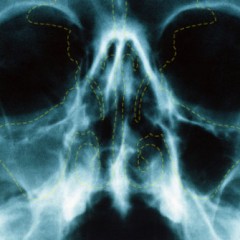

Sinusitis is the inflammation of the sinus, usually in the maxillary sinuses or the sinuses located in the cheekbone. Sinuses are the air-filled spaces found within the cheekbone and the forehead that will normally produce little amounts of mucus that drains through small channels into the nose. The most common cause for sinusitis is infection, either bacterial infection or viral infection. Viral infection can first cause the...